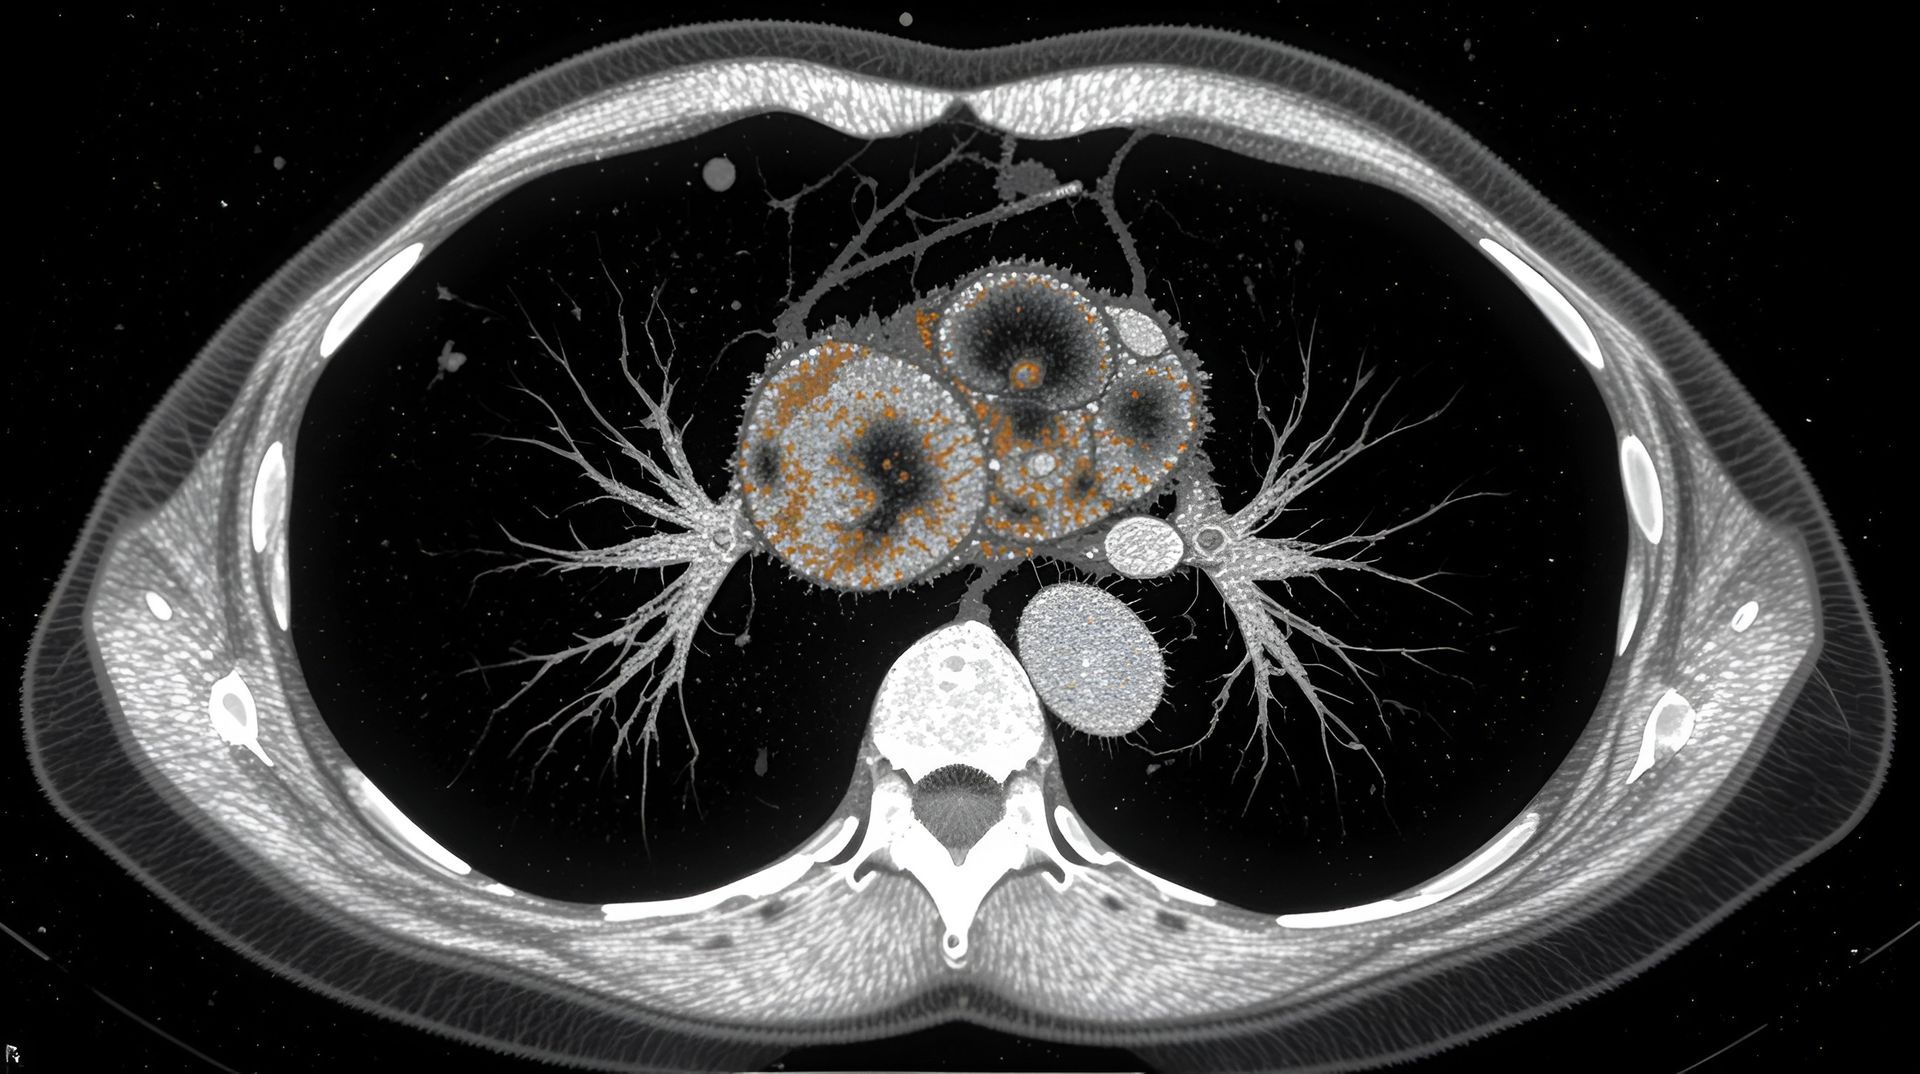

A evolução constante na área da cirurgia torácica tem proporcionado aos pacientes opções mais avançadas e menos invasivas para tratar diversas condições pulmonares. Entre as diferentes abordagens, destacam-se a cirurgia robótica, a videotoracoscopia e a tradicional toracotomia. Cada uma dessas técnicas possui suas características distintas em termos de via de acesso, equipamento utilizado e benefícios para o paciente.

Comparação das Incisões: Tamanho e Localização

A principal diferença entre essas abordagens reside no tamanho e na localização das incisões. Enquanto a cirurgia robótica e a videotoracoscopia buscam minimizar as incisões para reduzir o impacto no paciente, a toracotomia requer uma incisão maior para oferecer um acesso mais amplo.